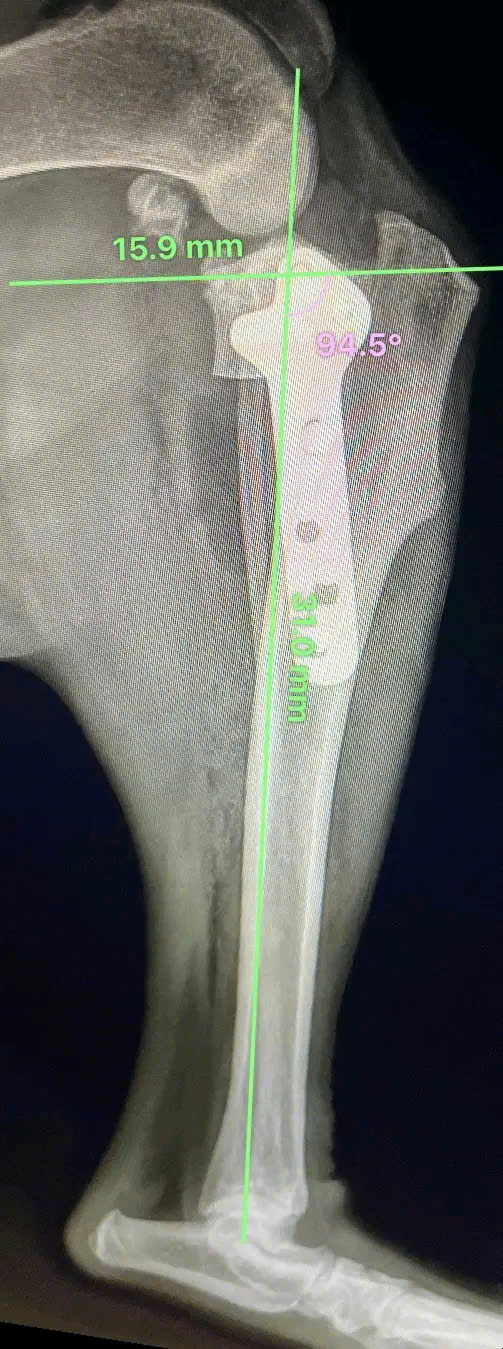

Hình ảnh thực tế

Khám phá không gian chăm sóc thú cưng chuyên nghiệp tại Bệnh viện Thú Y Gia Kiệm